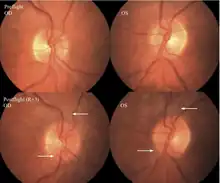

The first U.S. case of visual changes observed on orbit was reported by a long-duration astronaut that noticed a marked decrease in near-visual acuity throughout his mission on board the ISS, but at no time reported headaches, transient visual obscurations, pulsatile tinnitus or diplopia (double vision). His postflight fundus examination (Figure 1) revealed choroidal folds below the optic disc and a single cotton-wool spot in the inferior arcade of the right eye. The acquired choroidal folds gradually improved, but were still present 3 year postflight. The left eye examination was normal. There was no documented evidence of optic-disc edema in either eye. Brain MRI, lumbar puncture, and OCT were not performed preflight or postflight on this astronaut.[5]

The sixth case of visual changes of an ISS astronaut was reported after return to Earth from a 6-month mission. When he noticed that his far vision was clearer through his reading glasses. A fundus examination performed 3 weeks postflight documented a grade 1 nasal optic-disc edema in the right eye only. There was no evidence of disc edema in the left eye or choroidal folds in either eye (Figure 13). MRI of the brain and eyes days postflight revealed bilateral flattening of the posterior globe, right greater than left, and a mildly distended right optic nerve sheath. There was also evidence of optic-disc edema in the right eye. A fundus examination postflight revealed a "new onset" cotton-wool spot in the left eye. This was not observed in the fundus photographs taken 3 weeks postflight.[5]

The seventh case of visual changes associated with spaceflight is significant in that it was eventually treated postflight. Approximately 2 months into the ISS mission, the astronaut reported a progressive decrease in his near and far acuity in both eyes. The ISS cabin pressure, CO2 and O2 levels were reported to be within normal operating limits and the astronaut was not exposed to any toxic substances. He never experienced losses in subjective best-corrected acuity, color vision or stereopsis. A fundus examination revealed a grade 1 bilateral optic-disc edema and choroidal folds (Figure 15).[5]